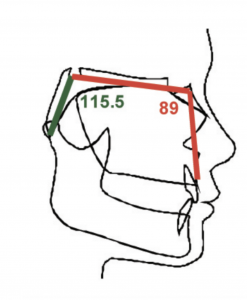

This kinda reminds me of the mew indicator line, indicator cheek line and what'd he go about evaluating SN line, FN plane and Cranial base angles

This kinda reminds me of the mew indicator line, indicator cheek line and what'd he go about evaluating SN line, FN plane and Cranial base angles

View attachment 4063432View attachment 4063433View attachment 4063434View attachment 4063436View attachment 4063438View attachment 4063439View attachment 4063440